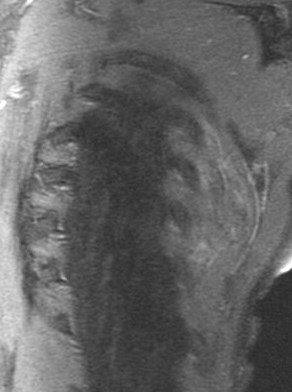

70 yo with 3 year history of slow growing mass in scapular region.

Typical location and dark appearance of this psuedotumor. Reference article.

Elastofibroma dorsi